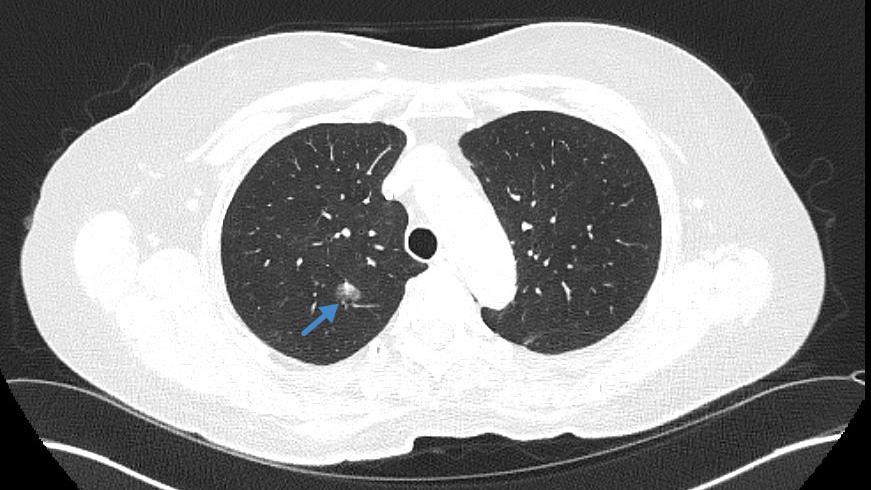

Beste Chancen dank früher Diagnose: CT-Aufnahme der Lunge einer älteren Patientin und ehemaligen Raucherin mit auffälligem Herd (siehe blauer Pfeil). Die weitere Abklärung ergab, dass es sich dabei um einen bösartigen Tumor handelt. Die Patientin konnte erfolgreich operiert werden und hat daher beste Aussichten dauerhaft geheilt zu sein. © TUM Klinikum

Beste Chancen dank früher Diagnose: CT-Aufnahme der Lunge einer älteren Patientin und ehemaligen Raucherin mit auffälligem Herd (siehe blauer Pfeil). Die weitere Abklärung ergab, dass es sich dabei um einen bösartigen Tumor handelt. Die Patientin konnte erfolgreich operiert werden und hat daher beste Aussichten dauerhaft geheilt zu sein. Aufnahme: TUM Klinikum. © TUM Klinikum